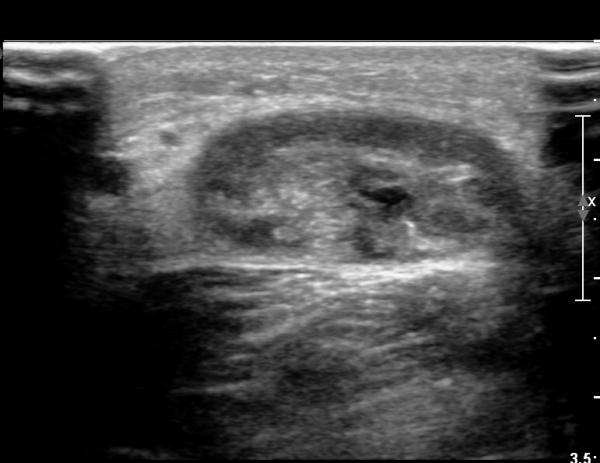

¾ÆÅ³·¹½º°Ç Á¾´Ü¸é°Ë»ç¿¡¼­ ¾ÆÅ³·¹½º°Ç ¸»´ÜºÎ¿¡ ¾ÆÅ³·¹½º°ÇÀÇ Àú¿¡ÄÚºÎÁ¾, ±¹¼ÒÀû ¿¬°á¼º ¼Ò½Ç,

¹ß¸ñ°üÀý ÈĹæºÎ¿¡ ¼ö¾×Àú·ù°¡ °üÂûµÊ(»çÁø 3, 4, 5).

¾ÆÅ³·¹½º°Ç ±ÙÀ§ºÎ Á¾´Ü¸é°Ë»ç¿¡¼­ ¾ÆÅ³·¹½º°ÇÀÇ Àú¿¡ÄÚºÎÁ¾, ±¹¼ÒÀû ¿¬°á¼º ¼Ò½ÇÀÌ °üÂûµÇ¾î

ÆÄ¿­ÀÌ ±¤¹üÀ§ ÇÑ °ÍÀ» º¸¿©ÁÜ(»çÁø 6, 7).